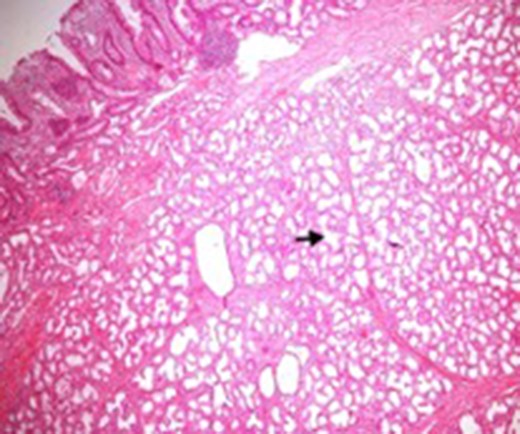

Microscopic appearance of Brunner’s gland hyperplasia. Arrow pointing at Brunner’s glands in the submucosa (stained by H & E).

Endoscopy can localize the lesion; however, biopsies are usually negative. Only a deep endoscopic or a surgical biopsy provides adequate tissue because the Brunner’s gland proliferations are usually covered by normal mucosa [10] (Figs 6 and 7). It is prudent to include a Brunner gland hyperplasia in a differential diagnosis while evaluating a duodenal mass, since it has varied presentation and bleeding is a common clinical sign masquerading other gastrointestinal conditions, e.g. gastrointestinal stromal tumours.